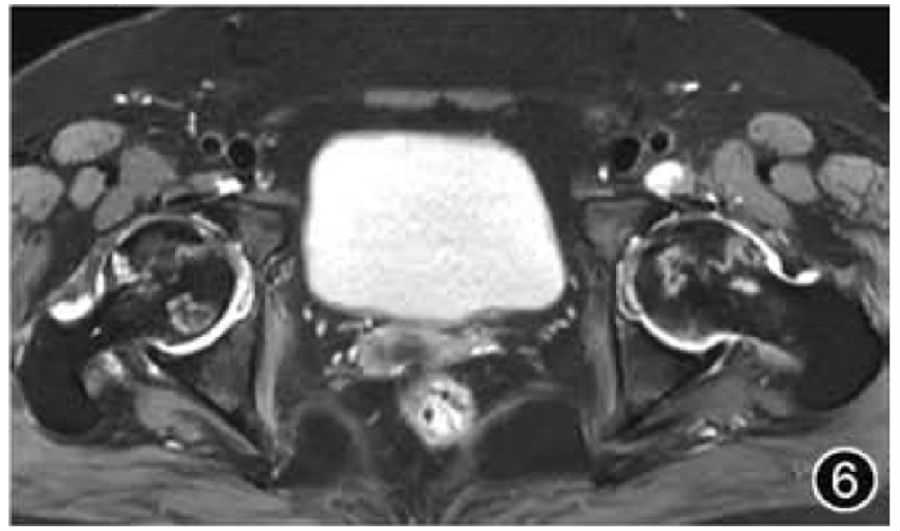

5.股骨头缺血性坏死:由于股骨头缺血性坏死往往是双侧发病,因此在影像检查时应选择双髋关节MRI检查,且应特别注意评估双侧髋关节的对称性。典型的股骨头缺血性坏死在MRI上表现为新月形软骨下病变,周围有低信号边缘,在T2WI上具有特征性的“双线征”(图6)。应描述骨坏死的位置和大小、受影响的股骨头体积的估计百分比(<15%、15%~30%、>30%)及病变所处阶段。由于股骨头塌陷代表更晚期疾病和不可逆转的损伤,因此股骨头是否出现塌陷应当描述(<2 mm为轻度,≥2 mm为中重度),若存在继发性髋关节OA和股骨头碎裂也应描述。骨坏死的主要信号可用于评估所处阶段,脂肪信号提示超急性或愈合期病变,骨髓水肿信号提示急性或亚急性期病变,而骨质硬化信号提示病变处于慢性期。

图6 股骨头缺血性坏死MRI图像。横断面T2WI示双侧股骨头见两条条带状内高外低并行高信号,为双线征